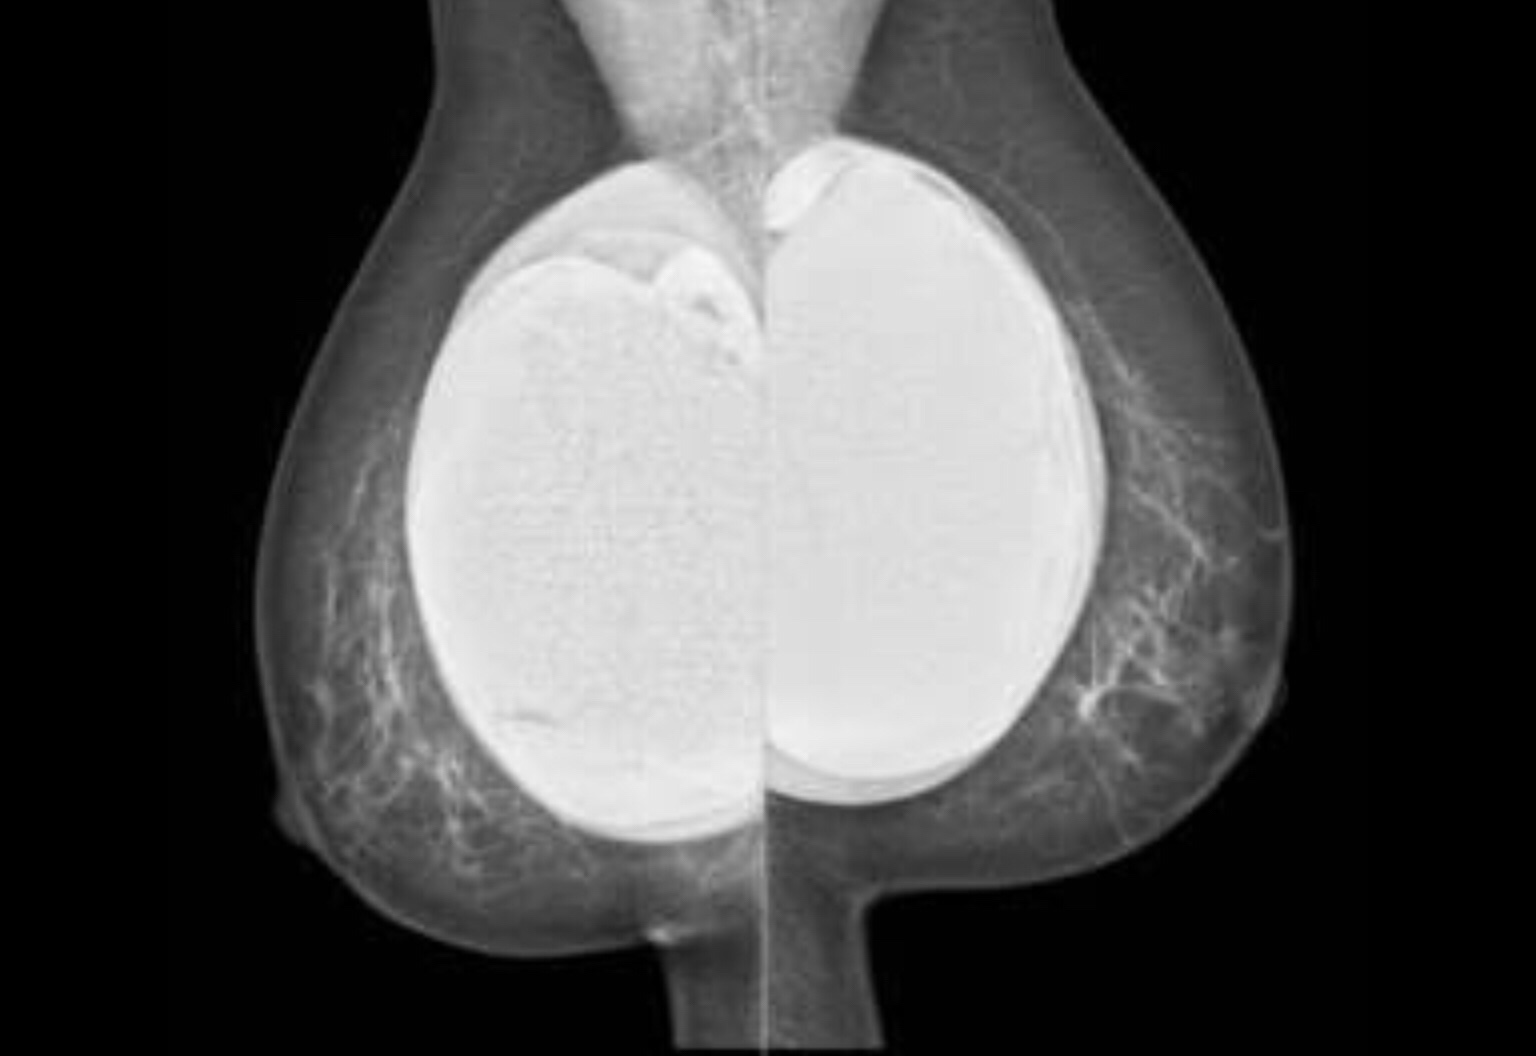

Breast Implants: Breast augmentation is one of the most common and popular cosmetic surgeries that women undergo. This is how they would appear on the mammogram.

Breast implants make mammography more difficult and can obscure small lesions. Mammography can also help detect implant related problems such as rupture, capsular contraction etc.